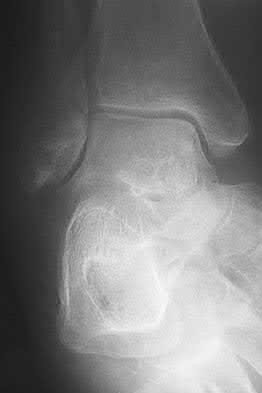

A 25-year-old female is involved in a motor vehicle collision. She presents with the isolated injury seen in Figures A through D. Her leg is swollen but her skin is intact. She has no clinical signs of compartment syndrome. Which of the following treatment options will allow for maintenance of fracture alignment and minimize the risk of soft tissue complications?

The patient presents with a closed distal third metaphyseal-diaphyseal distal tibia fracture with simple intra-articular extension. Immediate intramedullary nailing along with percutaneous fixation of the articular component provides appropriate restoration of length, rotation and alignment and minimizes the risk of wound complication.

Displaced distal third tibia fractures may be associated with simple intraarticular extension. Operative treatment of intra-articular distal tibia fractures has historically been performed with open reduction and internal fixation. Early open reduction and plate fixation of pilon fractures has been associated with high rates of infection and wound complication. In select patterns with simple articular extension, percutaneous screw fixation and medullary nailing may provide appropriate reduction with minimal soft-tissue risk.

Figures A and B demonstrate a distal third tibial shaft fracture with simple intra-articular extension. The axial and coronal CT cuts in Figures C and D further clarify the articular injury. Illustrations A and B demonstrate a comminuted distal third tibial fracture with simple intra-articular extension. Illustrations C and D are fluoroscopic images of the same injury after intramedullary nailing and percutaneous fixation of the articular component.